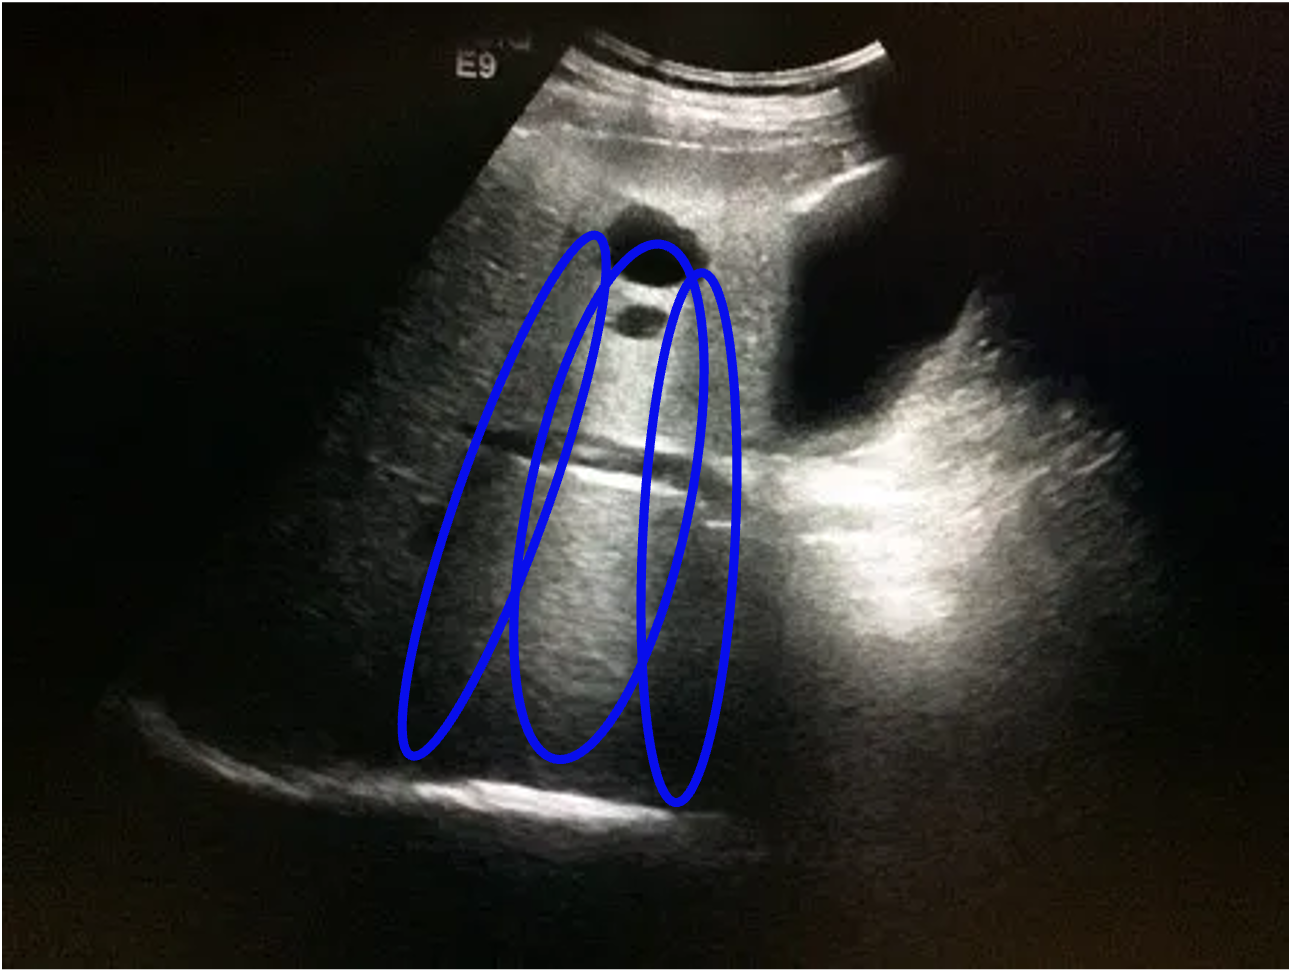

[10] Example ultrasound images with speckle noise(both), downward attenuation(both), shadows(blue regions left) and reverberation artefacts (blue lines right)

As is the case for many coherent imaging systems (systems in which waves can interfere with each other), the sensor unintentionally picks up unwanted signals that may come from the environment or the transducer itself. This leads to random overlaying patterns in the image. Speckle Noise in particular is the noise generated by the random scattering of transducer sound waves through the tissue. We can see this effect in both of the above images.

Highly reflective tissue or materials reduce the amount of transmitted sound waves that would pass to tissue more distant to the transducer. This leads to so-called shadowing regions that are particularly prune to noise signals coming from the surrounding tissue. Since sound waves will be dampened while passing through any kind of material, even a body with equal impedance will produce an image with a continuously darker growing shadow. This effect is called downward attenuation and can also be seen in the above images that both get darker in downward direction. An example for shadows can be seen inside the blue coloured circles in the left image.

In addition to shadowing regions, two reflective objects can also cause reverberation artefacts when light bounces back and forth between them, causing a repeating pattern. In the right image they are highlighted with blue color and generally appear as repeating pattern with equal distance.